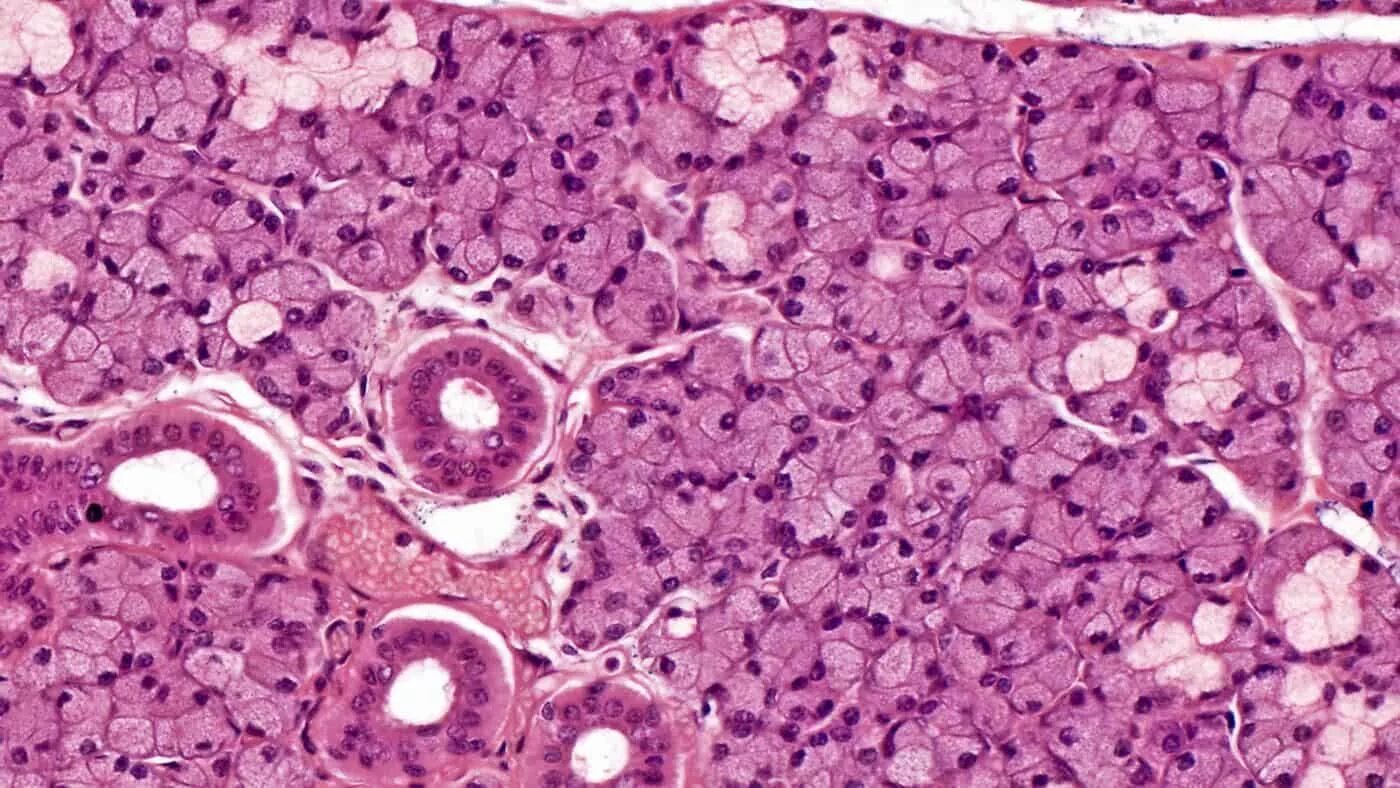

Фото тканей человека